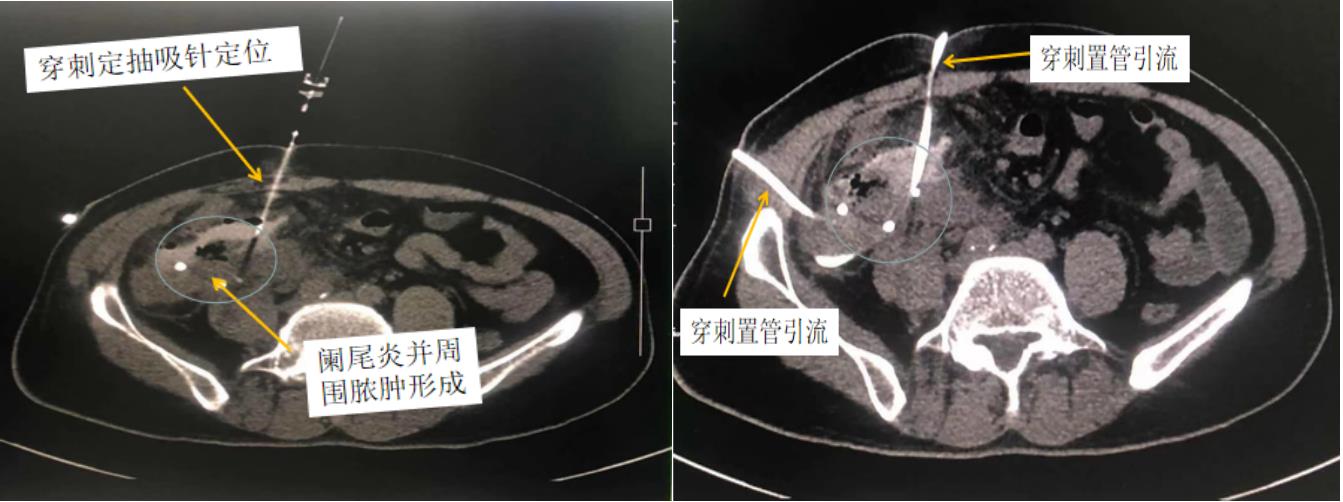

5、CT引導下置管引流術:對于臨床上各種原因引起的腹盆腔膿腫,可進行CT引導下置管引流術,準確定位病灶,并進行膿液引流、沖洗給藥,可盡快控制感染,控制病情。

圖5 闌尾炎并周圍膿腫形成CT引導下穿刺穿刺置管引流